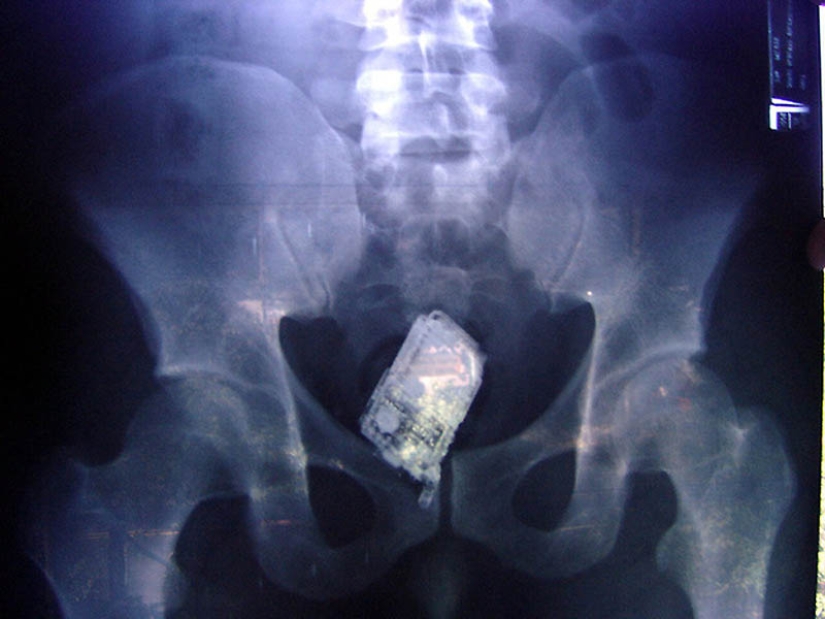

14. Mobile phone in the prisoner's intestines.